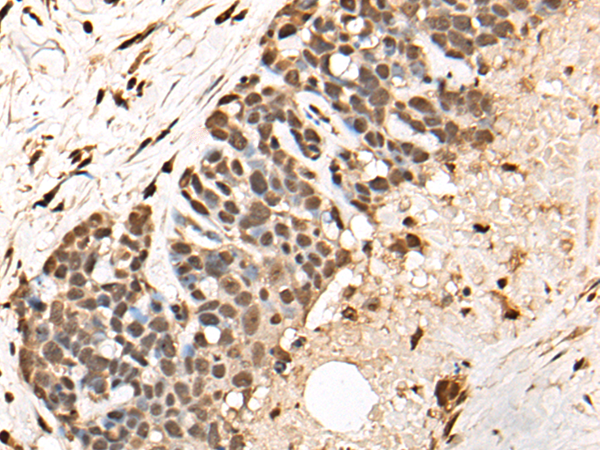

分类: 科研抗体货号: P02503别名: GARS; HMN5; CMT2D; DSMAV; GlyRS; SMAD1应用: WB,IHC反应种属: Human, Mouse, Rat